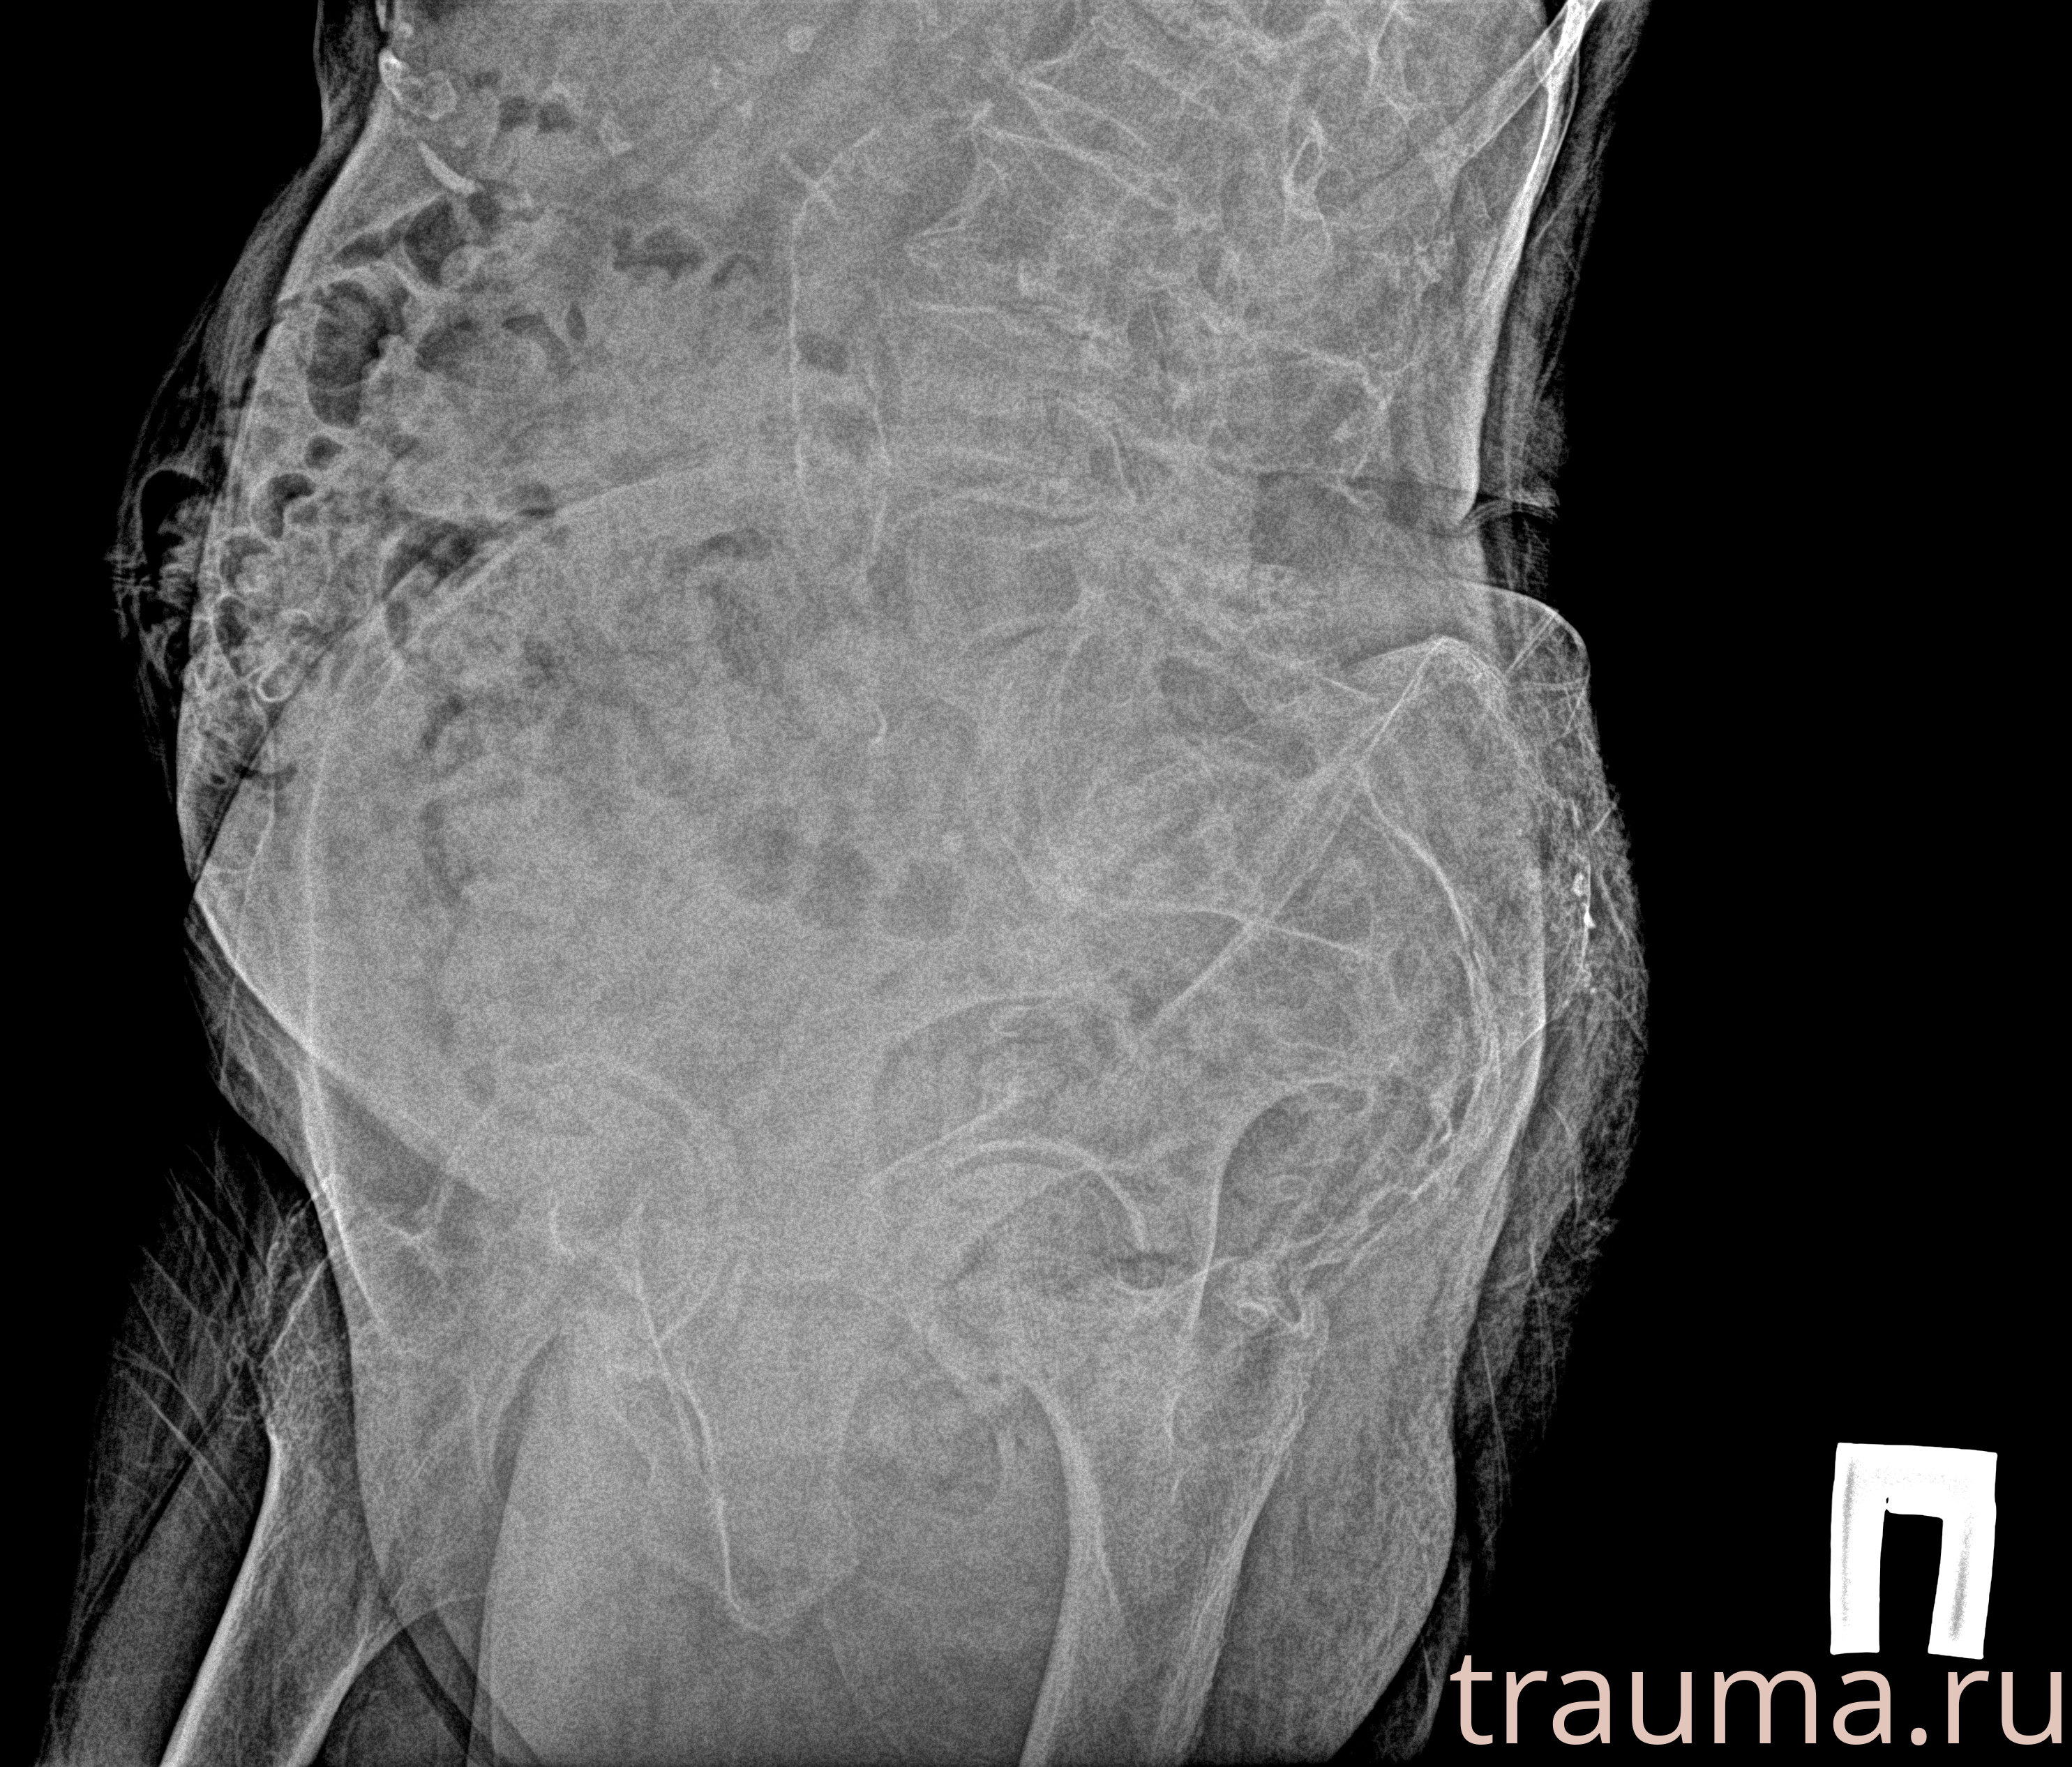

Рентген на дому: по вашему адресу приезжает врач-рентгенолог, травматолог-ортопед с мобильным рентгеновским аппаратом, проводит диагностику травмы или заболевания, делает необходимые рентгенограммы, дает рекомендации по дальнейшему лечению. Получить качественные снимки в домашних условиях возможно благодаря уникальной методике, разработанной МосРентген Центром для института  Склифосовского

Яркость: 1   Контраст: 1   Инвертировать: 0 Увеличение: 1

Перетаскивайте мышь вверх/вниз для контраста, влево/право для яркости. Прокрутка колесом изменяет масштаб. Нажмите Сбросить для возврата к исходному изображению. При увеличении держите мышь в той области, которую хотите рассмотреть.